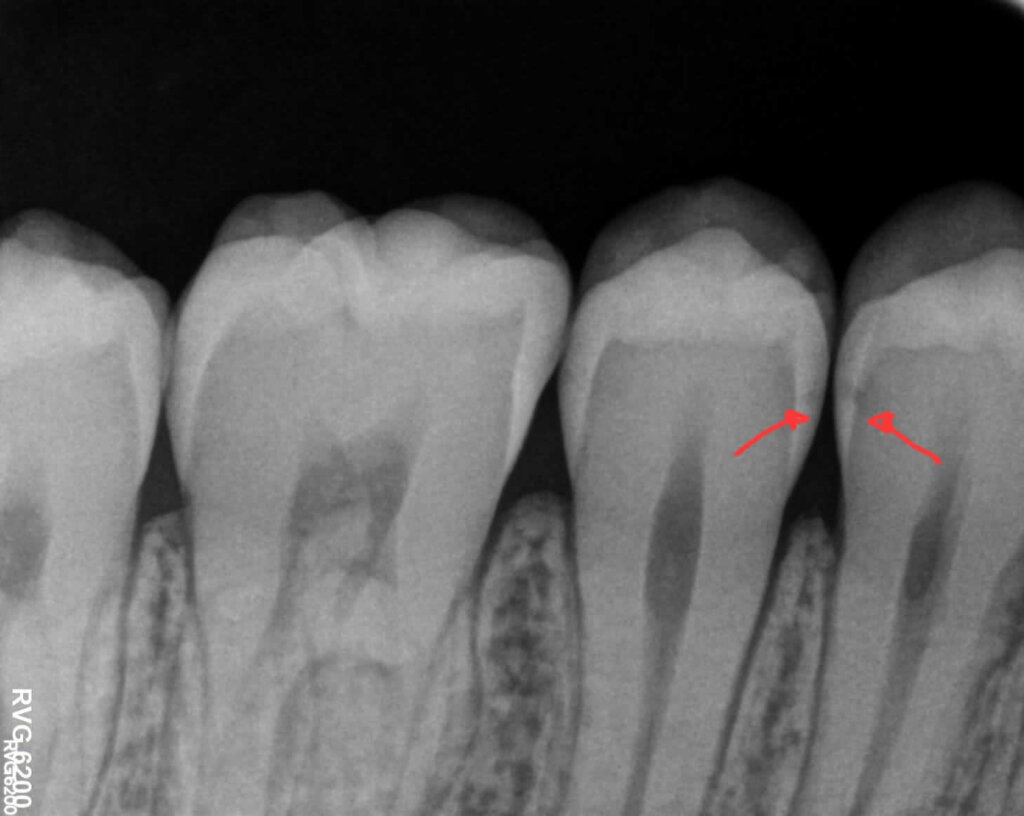

L'importanza della visita dentistica effettuata regolarmente: lesioni cariose allo stadio iniziale

Le carie nelle fasi iniziali spesso non provocano sintomi. Durante una visita di controllo il dentista può individuarle precocemente e trattarle con interventi semplici.